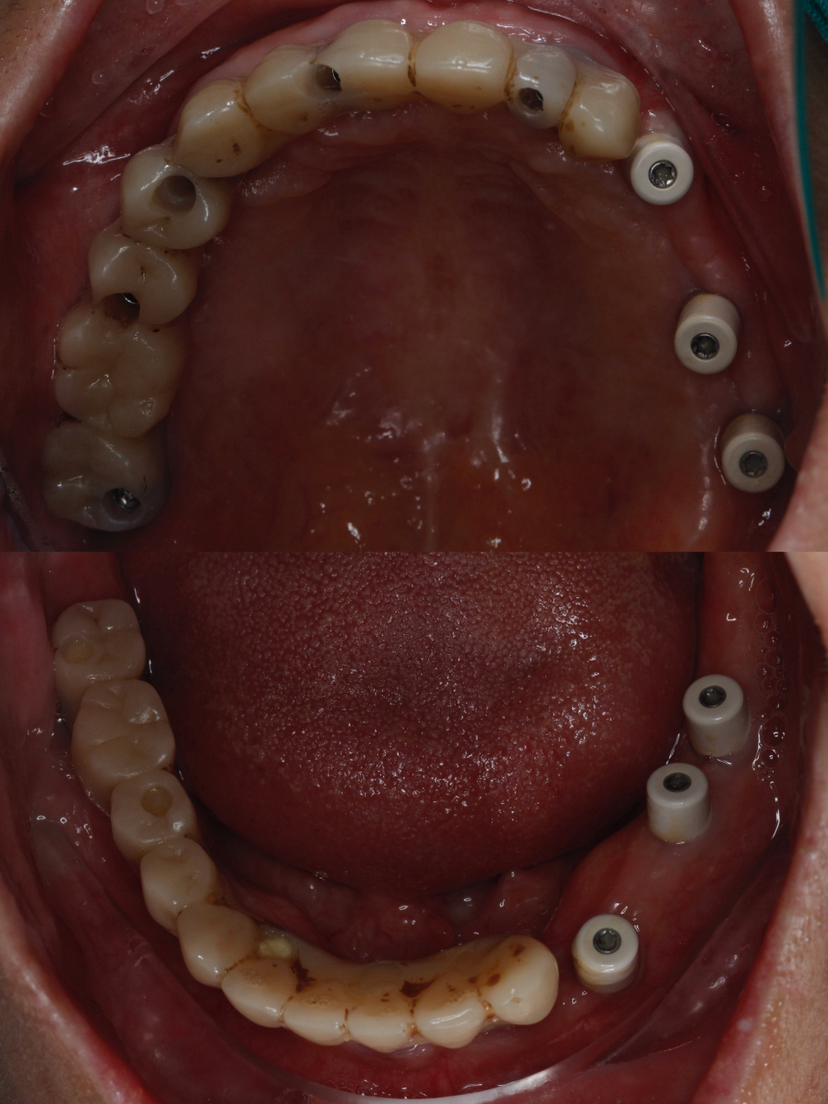

该患者就是因牙周病导致牙齿松动脱落,我们通过在全口牙槽骨上植入16颗种植体,然后在种植体上安装连桥牙冠,从而恢复半口牙齿的咀嚼功能和美观。相对于传统的种植修复方式缺一颗种一颗。4-8颗种植体的种植手术创伤相对较小,大大的减少了患者的疼痛感。